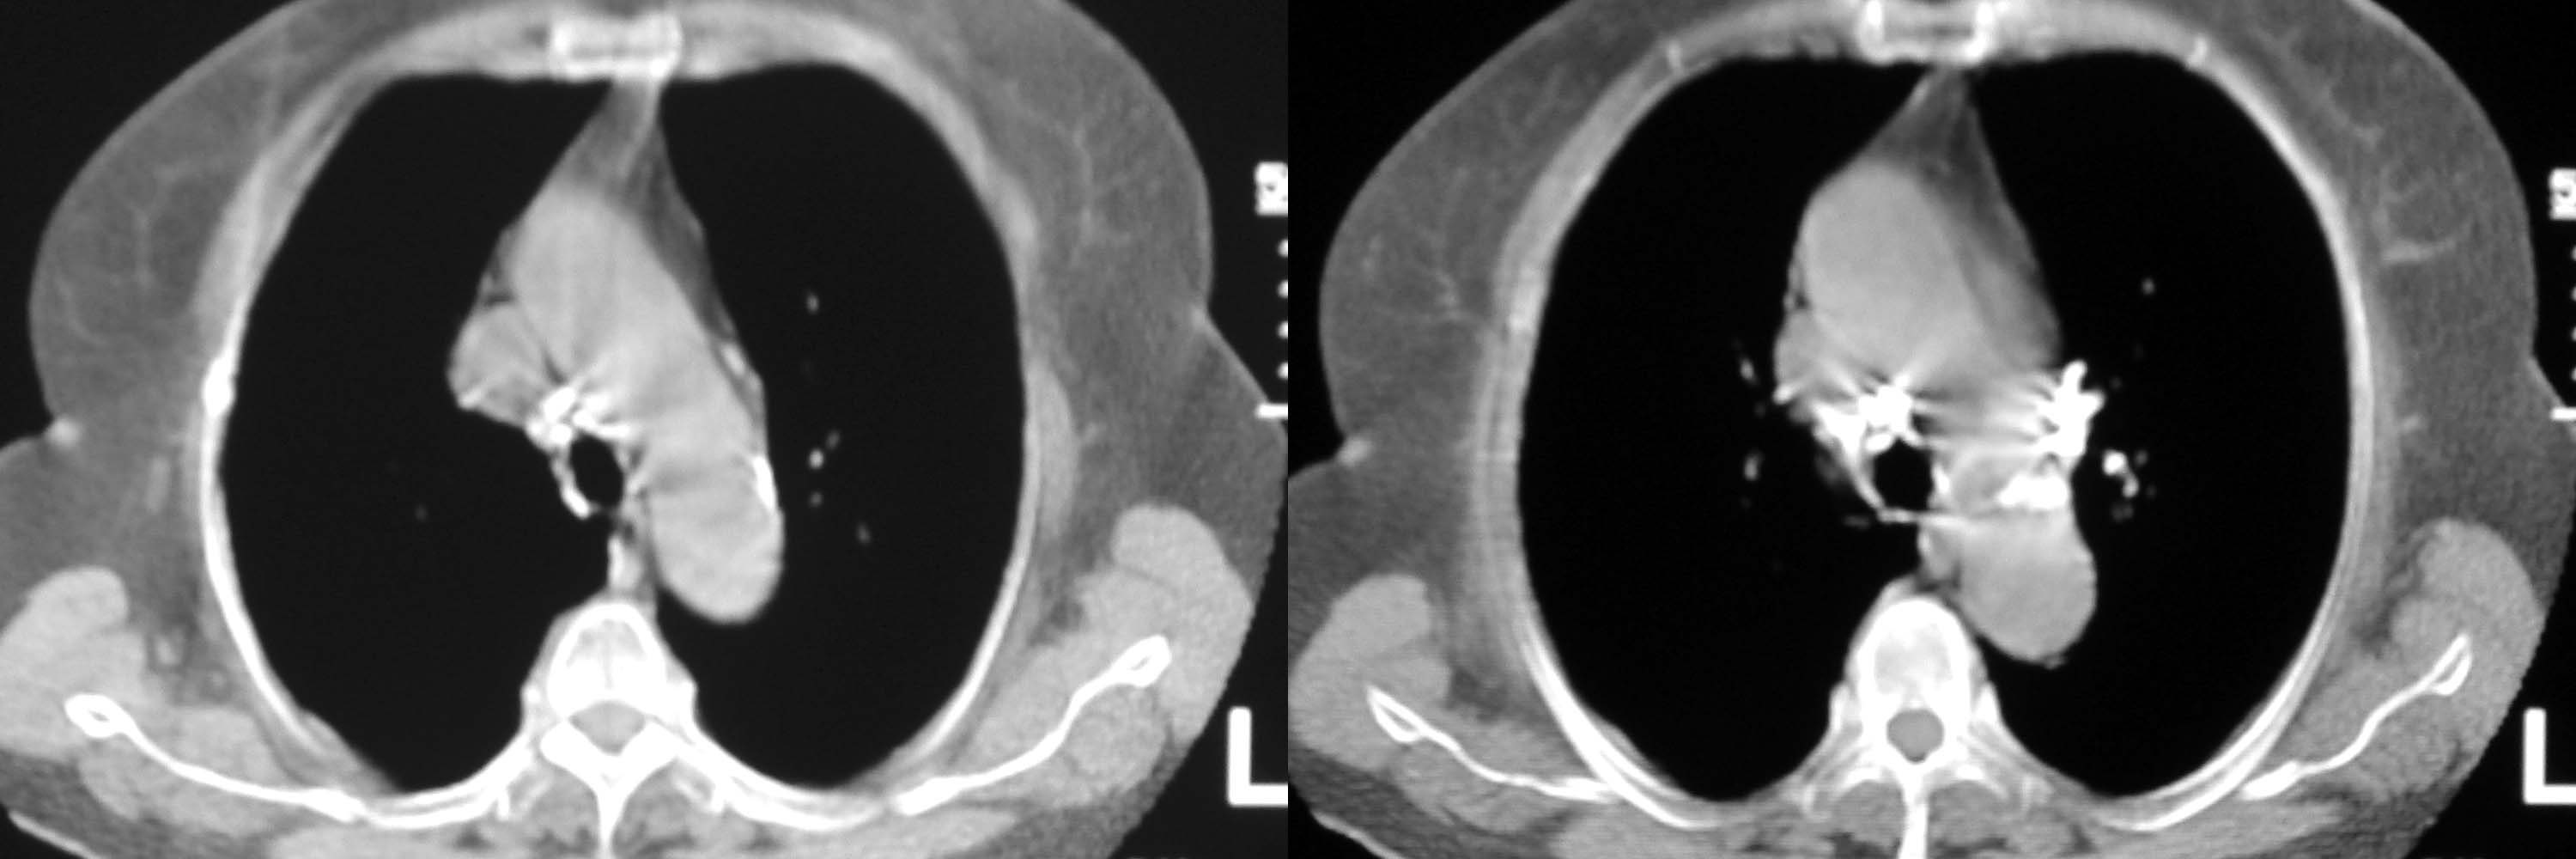

女78岁咳嗽咳痰无咳血平片报右上肺不张、慢支、肺气肿、请老师们帮忙看看,箭头所指是什么?是占位吗?有肺气肿吗?谢谢

箭头所指----多考虑-----右头臂静脉旁淋巴结钙化

可能是逾曲的头臂血管

可能是纡曲的头臂血管——支持。

箭头所指考虑血管影

箭头所指考虑血管影;纵隔内及双肺门区多发淋巴结钙化;不支持肺气肿。

箭头所指考虑血管影(头臂血管);纵隔内及双肺门区多发淋巴结钙化;不支持肺气肿。